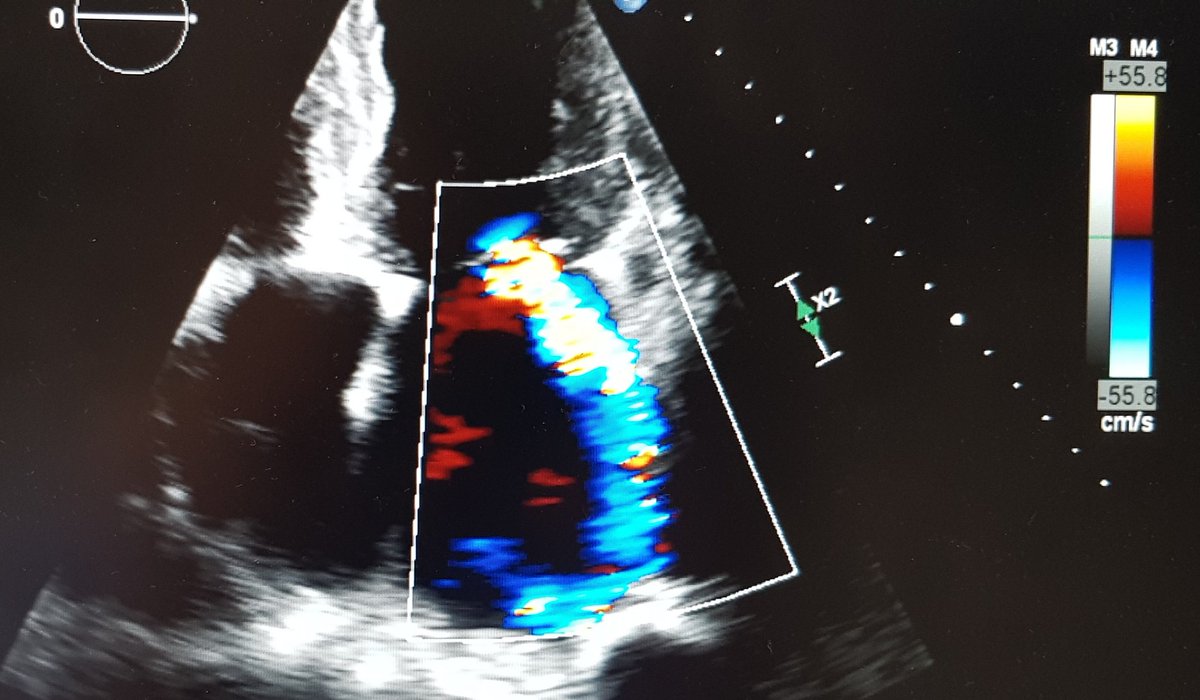

Here you can see the highly eccentric, posteriorly directed jet of MR

This is the AP3Ch view showing the same abnormality